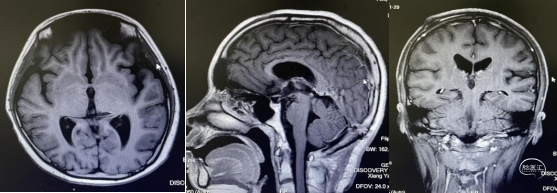

影像学资料显示

头部磁共振:松果体区可见一稍长-长T1、稍长-长T2信号灶,内可见小片状短丁1信号,增强后实性成分明显不均匀强化,大小约30mmx24mmx33mm,病灶部分伸入第三脑室,第三脑室扩张,双侧丘脑受压移位,中脑导水管,以慕上脑室系统积水扩张,双侧脑室旁可见线样FLAIR高信号。左侧丘脑,左侧脑桥及桥臂可见小片状长T1长T2信号,FLAIR呈高信号。